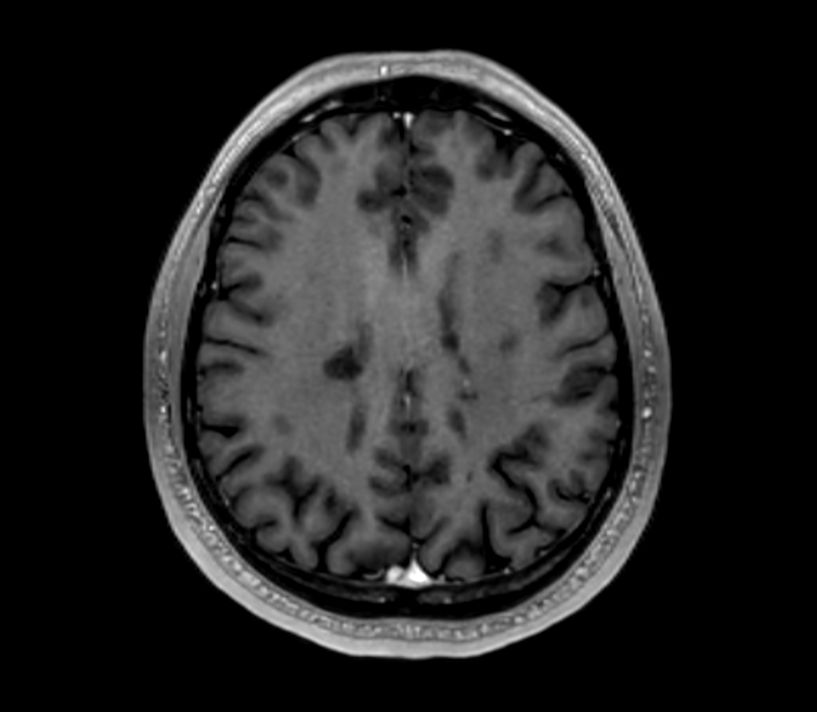

Brain - White matter lesions

Fast and high quality brain imaging for a patient with white matter lesions. AI based SmartSpeed is utlized to shorten scan time without compromise in image quality. Advanced 3D TSE imaging technique are used to acquire high resolution data in multiple directions in only one single scan.

Coronal T1w SEPre-Gado